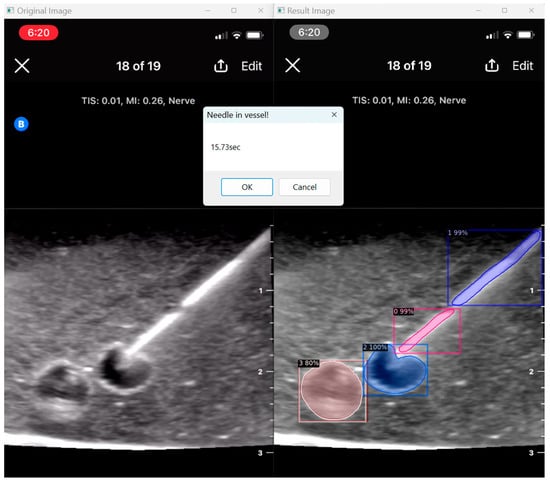

When the model is applied, the original ultrasound image is overlaid with a new layer that presents the detection results, offering insights into predicted target areas (Figure 4 and Figure 5).

The segmentation area represents the region identified by the model as each object class (needle tip, needle body, blood vessel, or nerve bundle). This area is visually highlighted, allowing for a clear understanding of what structure is of interest. To provide additional context, a bounding box in the shape of a square is placed around the segmentation area, enclosing the detected object and providing a concise representation of its location. These are illustrated in Figure 4, Figure 5 and Figure 6, with original images on the left and overlayed images on the right for our three different phantom models.

In order to assess the confidence level of the model’s predictions, a confidence percentage is assigned for each object class labelled (Figure 4, Figure 5 and Figure 6). This percentage represents the probability of a true positive detection by the model. It quantifies the model’s level of certainty regarding the accuracy of its prediction for each detected defect.

3.5. User Assessment

Our program presents an opportunity to automate ultrasound skill assessment over time, testing parameters like user speed (time taken for target structure penetration; Figure 9) and accuracy. With the automated segmentation of needle tip (item class 0) apart from needle body (item class 1), our program has the capacity to assess the percentage of frames for which a user keeps the full needle (including the tip) in view during their procedure. The capacities of AI in further assessment are vast, and possible features that can be expounded on include testing probe positioning and needle angulation.

Figure 9. User speed assessment.